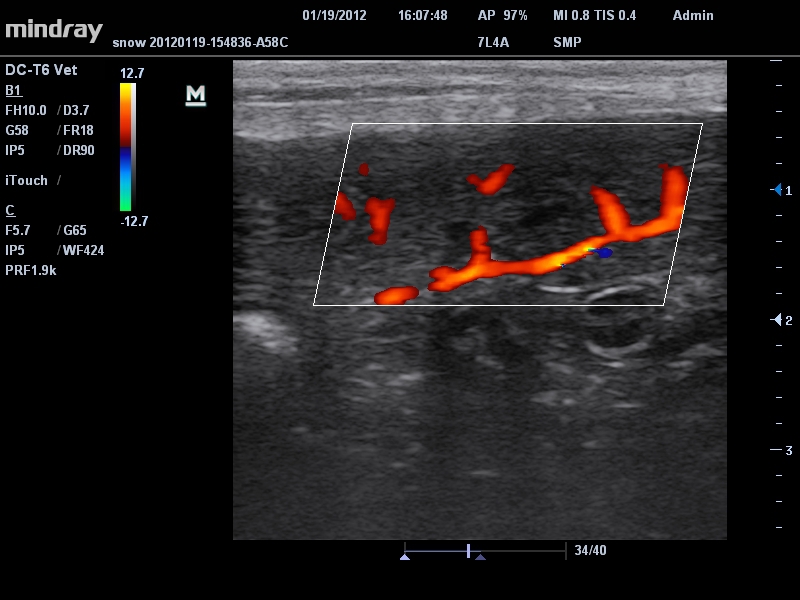

• Линейный ультразвуковой датчик Mindray 7L4A

• Режимы сканирования: B/M/CFM/PDI/Направленный PDI/PW, HPRF, Тканевая гармоника, М- и цветной М-режим.